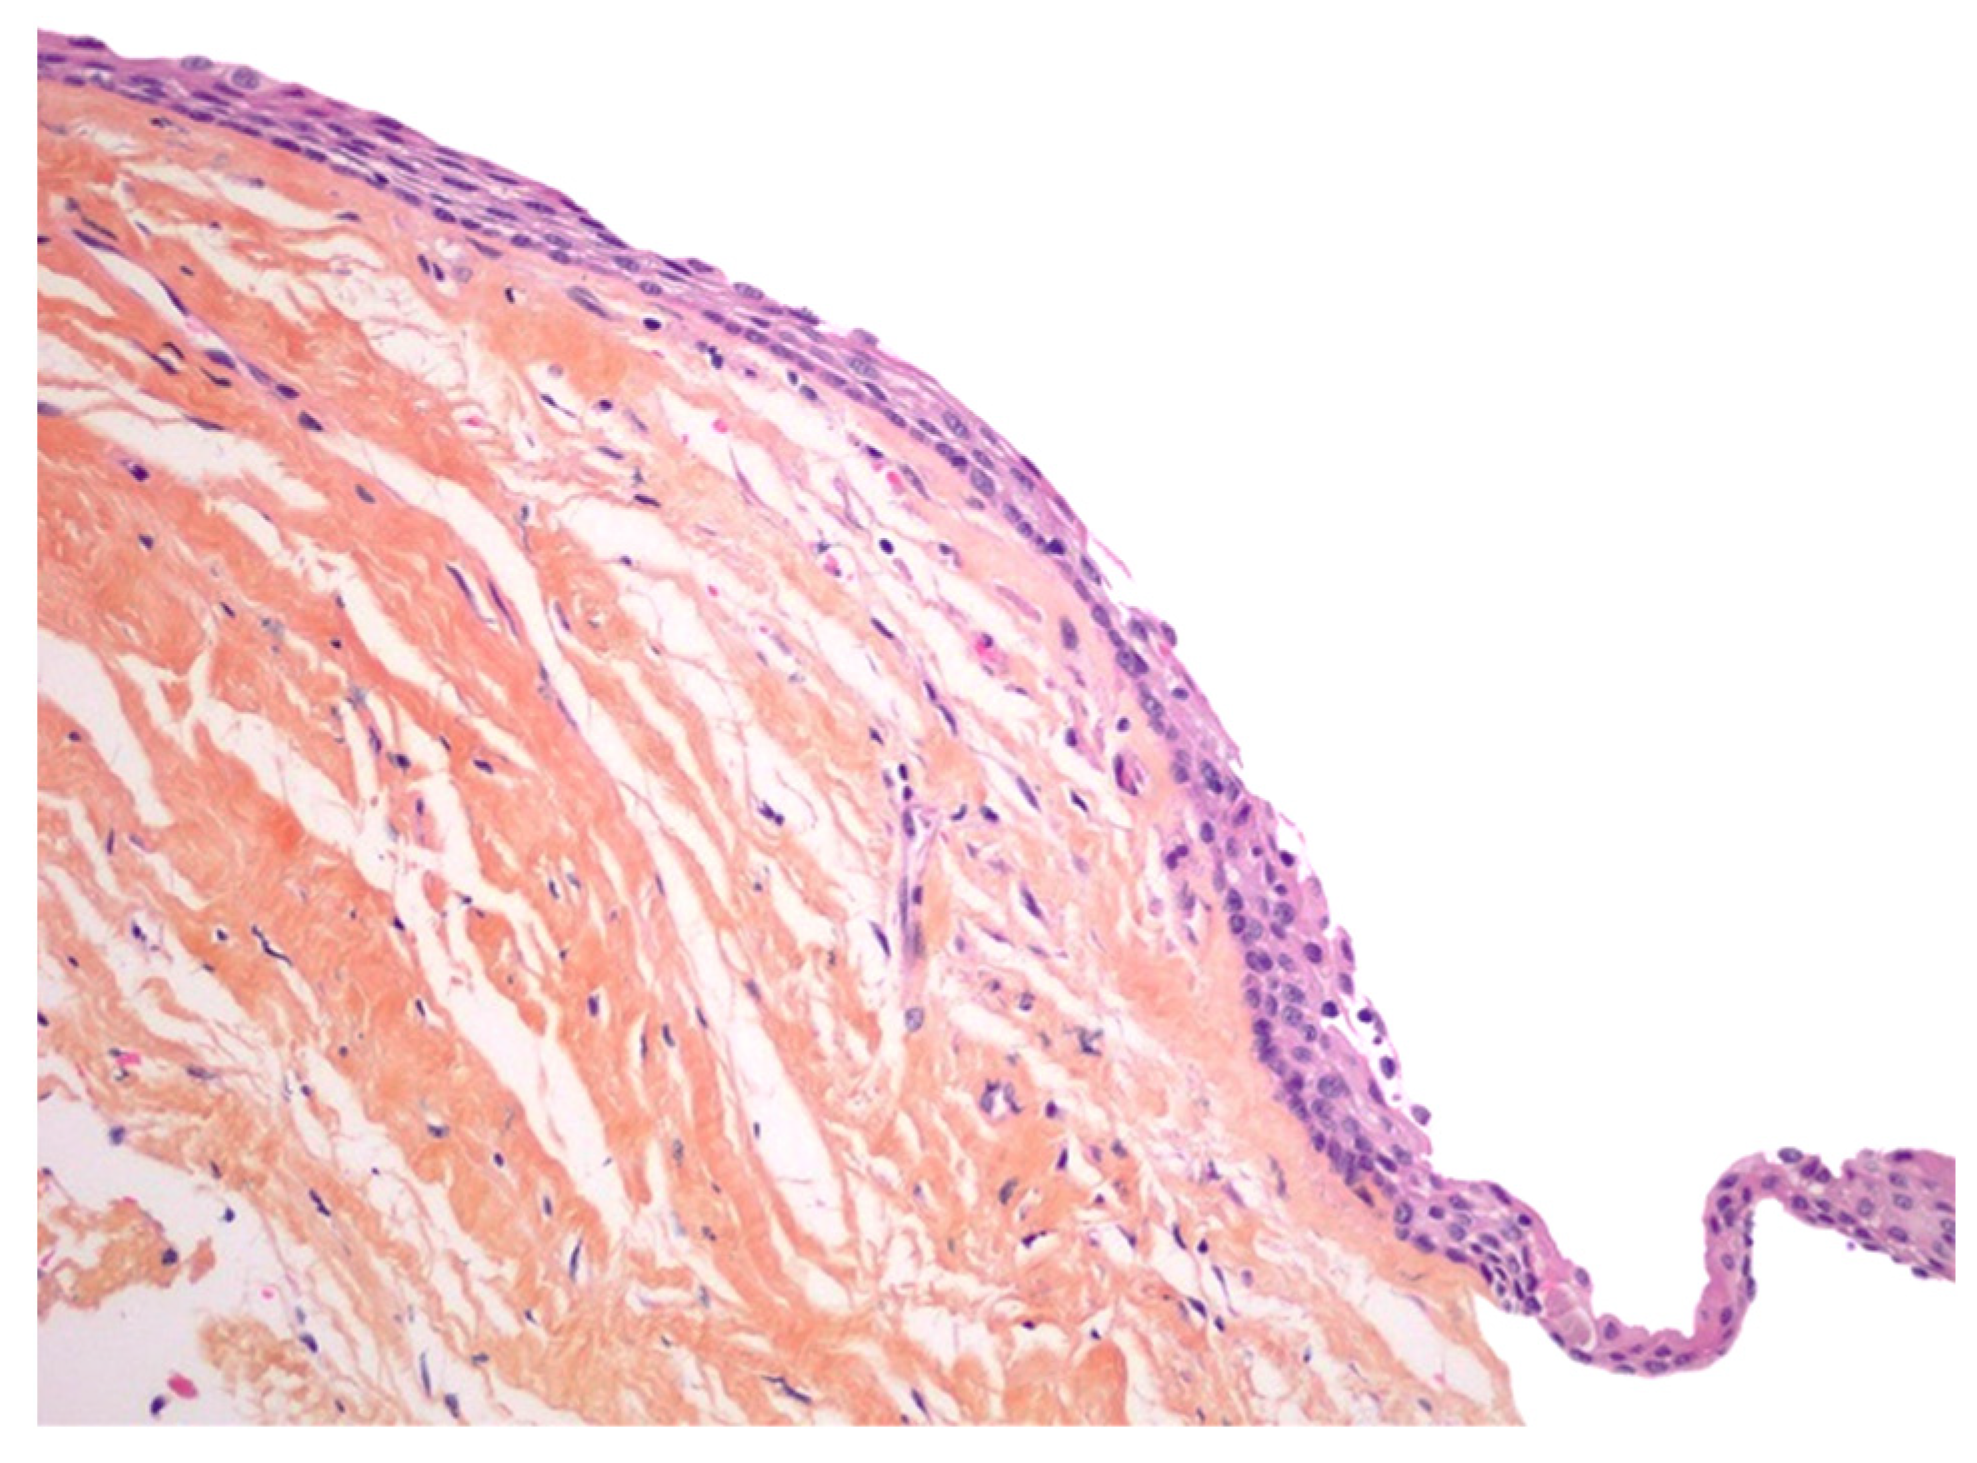

2. Case Presentation

3. Discussion

| Present Case | M | 46 | Pain | Maxillary distomolar | Enucleation |